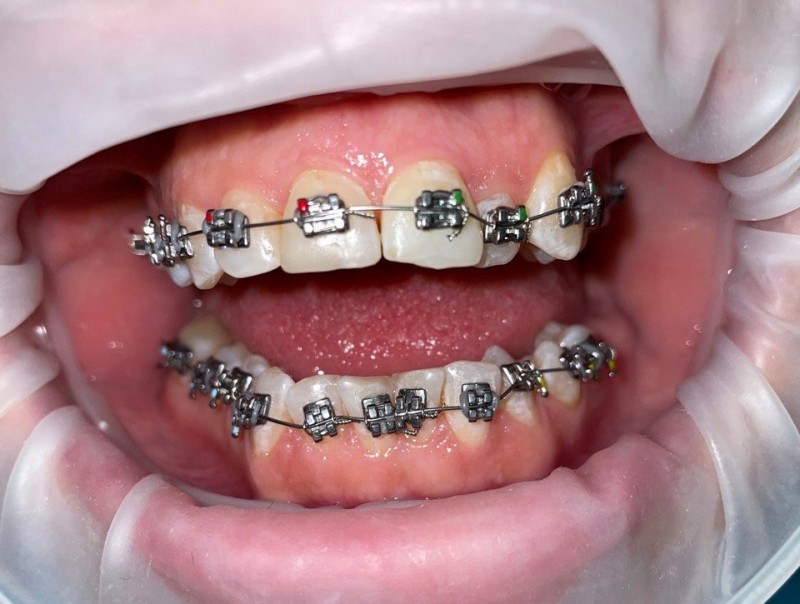

Установка брекетов Damon

Фото на этапе лечения через 4 месяца, брекеты Damon Q

Доктор: Жвания Нала Анзоровна